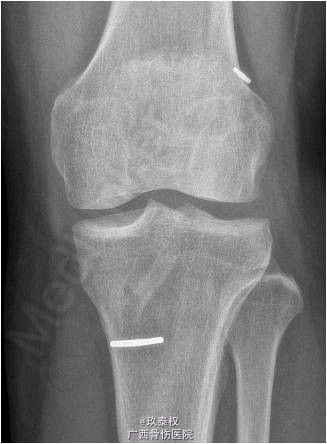

患者女,31岁,因“左膝关节前交叉韧带重建术后半年余,依约返院”入院。患者半年前在我院行“左膝关节镜检,前交叉韧带重建(后外侧束),内侧半月板修补(9针),内侧皱襞切除,门形钉固定术”。现患者依约返院行门型钉拆除术。

查体:双下肢无畸形,左膝关节无静脉曲张、肿胀等,皮温正常,关节间隙压痛,麦氏征(-),蹲走试验(-),过伸试验(-),过屈试验(-),浮髌征(-),髌骨加压研磨试验(-),前抽屉试验(-),后抽屉试验(-),侧方应力试验(-),lachman征(-),关节活动度0-135度,股四头肌无明显萎缩,肌力正常;肢端血运、感觉、活动正常。右下肢及双上肢其余关节未见明显异常。 辅助检查:X线平片及MRI检查未见明显异常。

诊断:1.左膝关节前交叉韧带重建术后;2.左膝关节半月板修补术后。行左膝关节镜检及门型钉拆除术。术后开始行股四头肌肌力训练及踝泵训练,术后第2天开始主动关节屈伸训练,屈膝达90°,术后第3天可完全负重。